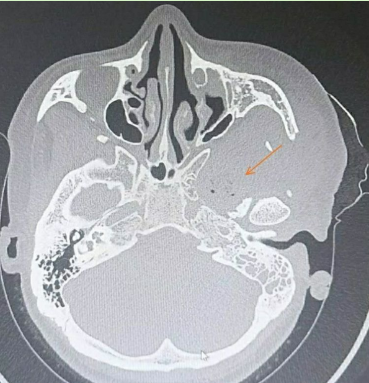

术前CT显示肿瘤和扩大的卵圆孔

结合术前颞骨CT薄层扫描+增强核磁,我们应该选择入路?